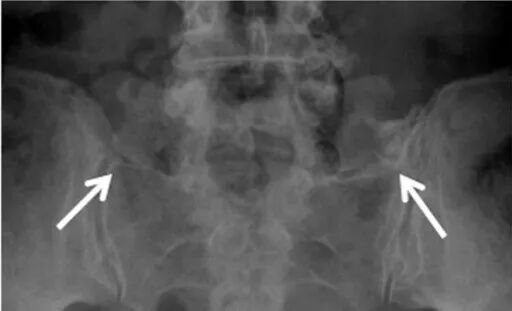

如果是正位X线平片,如果不采用特殊体位,恐怕价值不大,因为腰5横突会和骶骨嵴重叠在一起导致观察不清;在常规正位片基础上倾斜30°拍摄(AP radiograph with a 30°cranial angulation),称之为弗格森(Ferguson)射线片,此体位能够清楚显示腰5横突,是国外诊断Bertolotti综合征的首选检查方法。

(白箭指向假关节,但很难清晰显示)